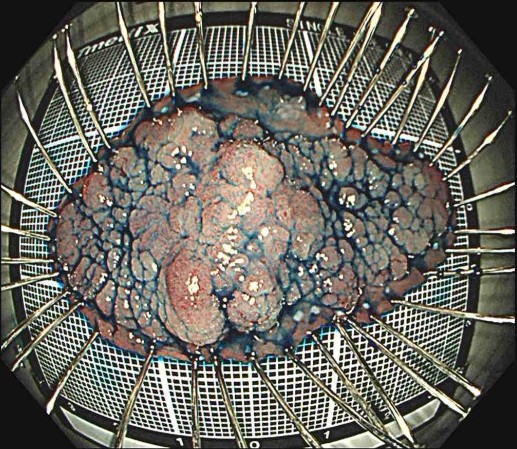

ESDの手順

Figures adapted from: Nagata M. Endoscopy 2024; 56: E699–E700.

Licensed under CC BY 4.0 (https://creativecommons.org/licenses/by/4.0/)

- 大きな病変でも一括切除が可能

- 正確な病理診断ができる

一括切除

は「がんを確実に治す」「正確に病理診断する」ために重要なポイントです。